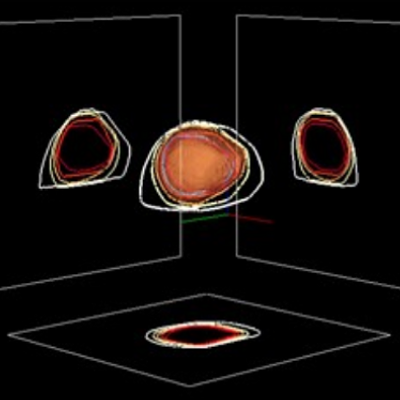

Jeroen Vendrik, Emile Farag, Niels de Hoon, Jolanda Kluin, and Jan Baan

Presence of aortic root vortex formation after TAVI with CENTERA confirmed using 4D-flow magnetic resonance imaging

Int J Cardiovasc Imaging

, 2018

more